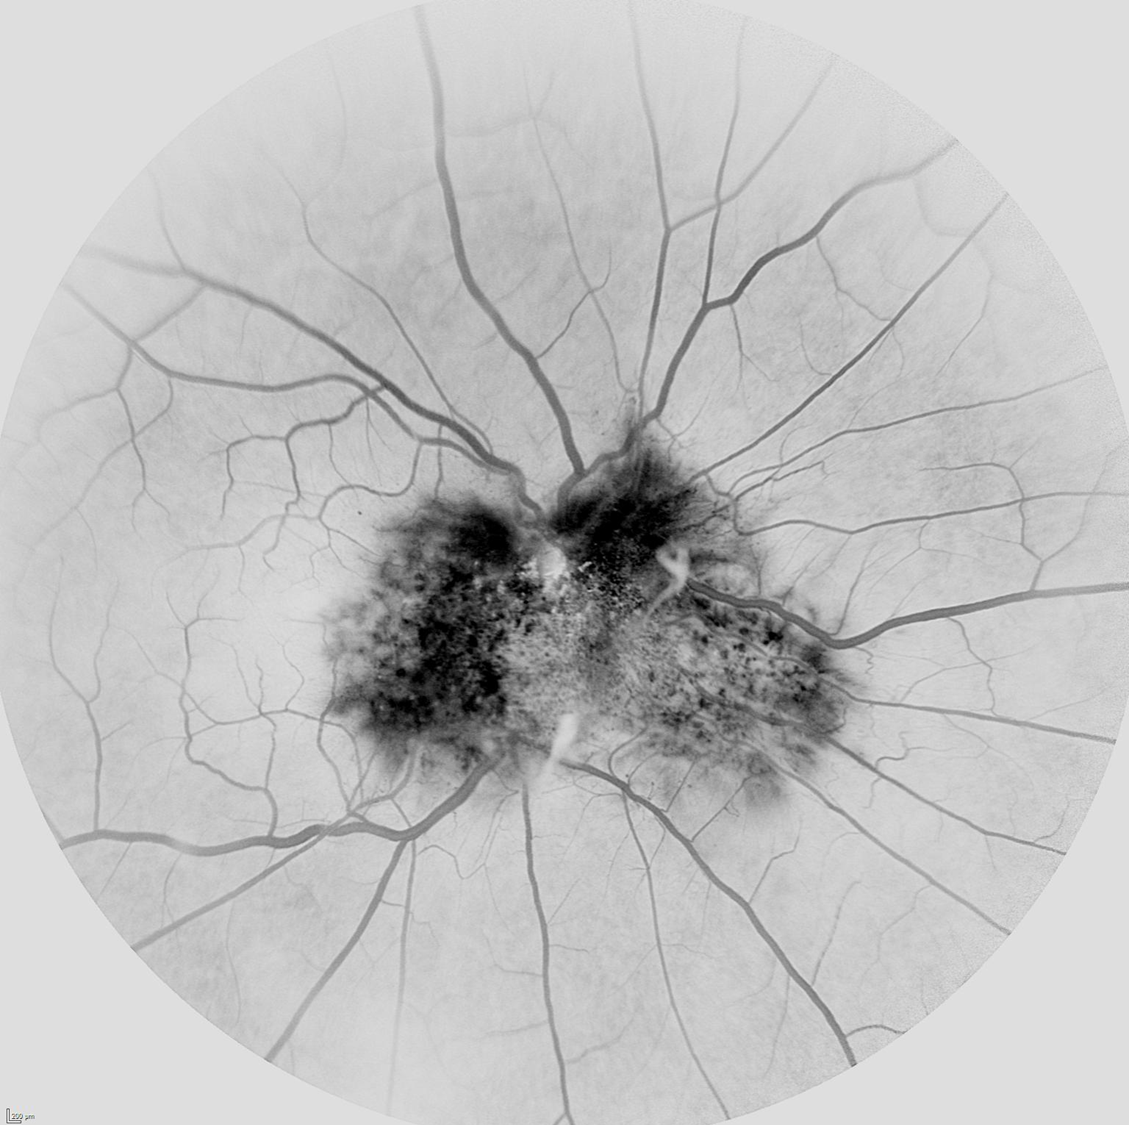

La angiografía puede ayudar bastante en el diagnóstico observándose en las fases precoces hipofluorescencia en relación al grado de hiperpigmentación del tumor, tortuosidad vascular y telangiectasias. En la fase media se observan mejor las anomalías vasculares y según avanzan los tiempos los vasos suelen fugar dando lugar a una hiperfluorescencia tardía.